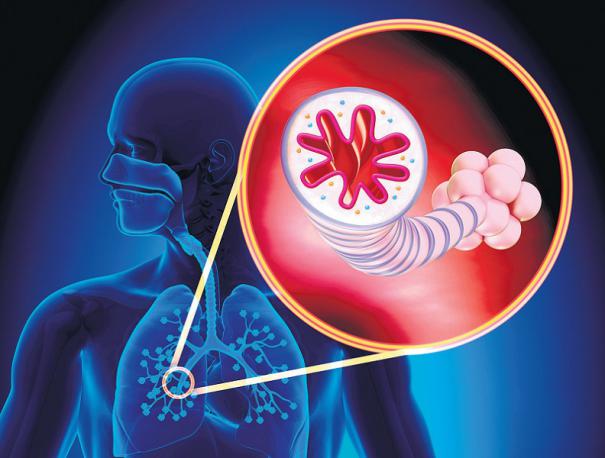

நுரையீரலுக்குப் பிராண வாயுவை எடுத்துச் செல்லும் நாளங்களை வீங்கவும் சுருங்கவும் செய்வதன் மூலம், இழுப்பு, மூச்சுத் தடை, மார்பு இறுக்கம், இருமல் போன்றவற்றை ஆஸ்துமா நோய் ஏற்படுத்தும். மூச்சு செல்கிற பாதையில் ஏற்படுகிற அழற்சியே இந்த நோயை உண்டாக்குகிறது.

ஒருவருக்கு இந்த நோய் வந்தால், மூச்சு செல்லும் பாதையானது வீக்கம் அடைந்து, அந்தப் பகுதியில் உள்ள தசைகள் இறுகுகின்றன. இதனால் அங்குப் பிராண வாயு செல்வது குறைகிறது. ஒவ்வாமை, ஒவ்வாமை ஊக்குவிப்பான்கள் இதற்கு முக்கியக் காரணங்களாகக் கருதப்படுகின்றன.